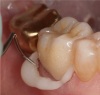

Using a retraction cord and retraction paste together may offer very good results. Compression caps, when used in conjunction with pastes, force the paste somewhat subgingivally and also contribute pressure to stop bleeding (Figure 5). Pastes are recommended to be kept in place for a minimum of 2 minutes and a maximum of 5 minutes. Leaving the paste in place for more than 5 minutes may not prove to be more effective. With the active ingredient in most pastes being an aluminum chloride, allowing the paste to remain longer than 5 minutes could result in irritation of the tissues and promote further bleeding.

Fig 5. For retraction paste to reach subgingivally and to facilitate pressure to stop bleeding, compression caps are used.

Figure 5